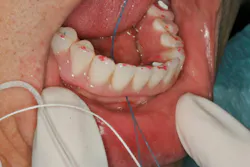

One of the most important steps that you can take to improve the chances of patients adequately maintaining their oral hygiene is to set up your plan for success from the beginning. Patients are often referred to my practice with complications after the delivery of their final prosthesis. A common origin of these complications is inadequate vertical height for the bridge. Aside from this resulting in fractures of the bridge, it is also the primary source of creating a concave intaglio surface (figure 2).

Figure 2: Concave intaglio = hygiene nightmare

The patient whose bridge is shown in Figure 2 returned to her dentist after the final bridge was placed complaining of speech difficulty and pain. The dentist told her everything was normal and that she needed to adapt to the bridge. Three months later, the patient presented to my office. The speech issue was legitimate in my opinion (that’s a story for another day), but I was concerned about the sensation of pain.

I removed the bridge to find the intaglio packed with food debris. The patient’s tissue was inflamed (figure 3), and she had developed a fungal infection. This could have been avoided with better presurgical preparation, adequate bone reduction, and proper vertical space development, which would have allowed the lab to make a hygienic intaglio (figure 4). Note the smooth and flowing intaglio surface in Figure 4. This is a bridge that can be easily maintained by the patient and hygienist.

Figure 3: Inflamed tissue from an inability to clean under the bridge